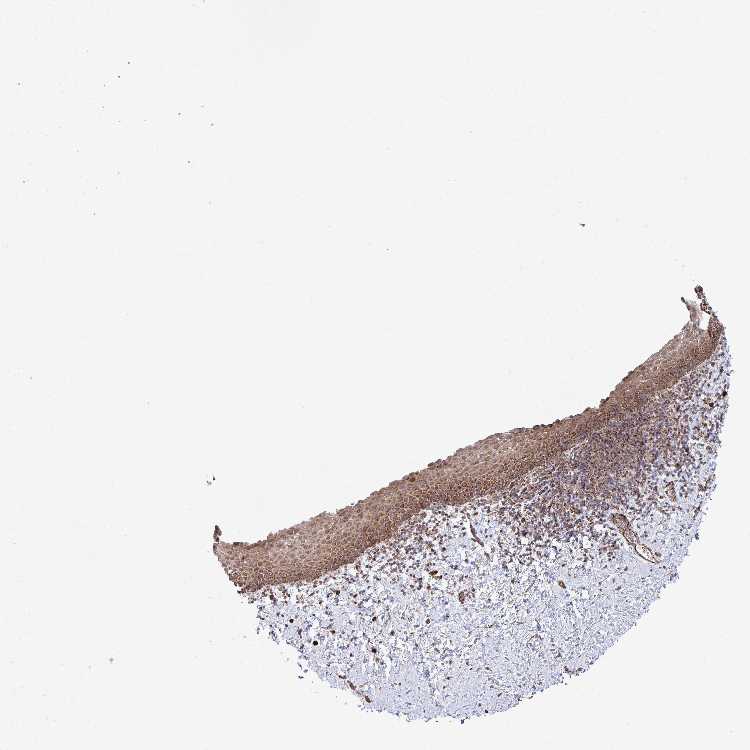

TISSUE PRIMARY DATA VAGINA Show tissue menu

Vagina

VAGINA - Antibody stainingi

Antibody staining in the annotated cell types in the current human tissue is reported as not detected, low, medium, or high, based on conventional immunohistochemistry profiling in selected tissues. This score is based on the combination of the staining intensity and fraction of stained cells.

Each image is clickable and will lead to virtual microscopy that enables deeper exploration of all samples and also displays staining intensity scores, fraction scores and subcellular localization as well as patient and tissue information for each sample.

Antibody HPA030761Antibody HPA056168

Squamous epithelial cells HighMedium